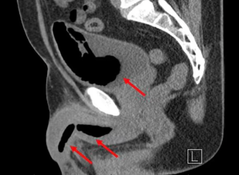

When the foam hardened the man was left with several masses inside his penis and bladder. A CT scan later revealed some of them were up to 11cm long and 4.3cm wide.